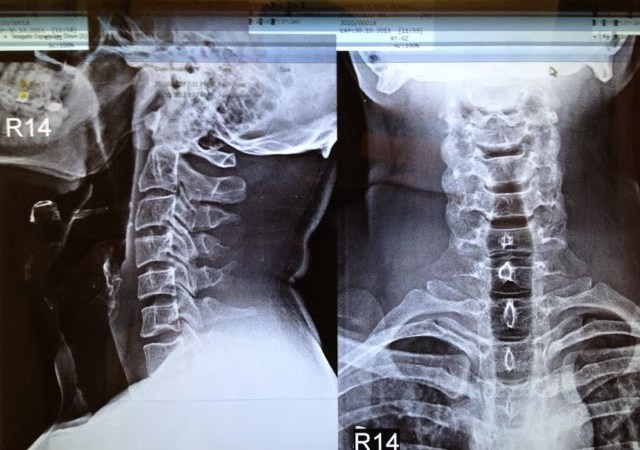

![]() |

| the loss of cervical lordoiss is still there but only due to muscle spasms – that should go away now with some muscle relaxants. a slight scoliosis of the spine is still evident, am working on that with regular physiotherapy. There is no sign of any defibrillated cartilage anymore and nothing is jutting into the spinal cord anymore. |